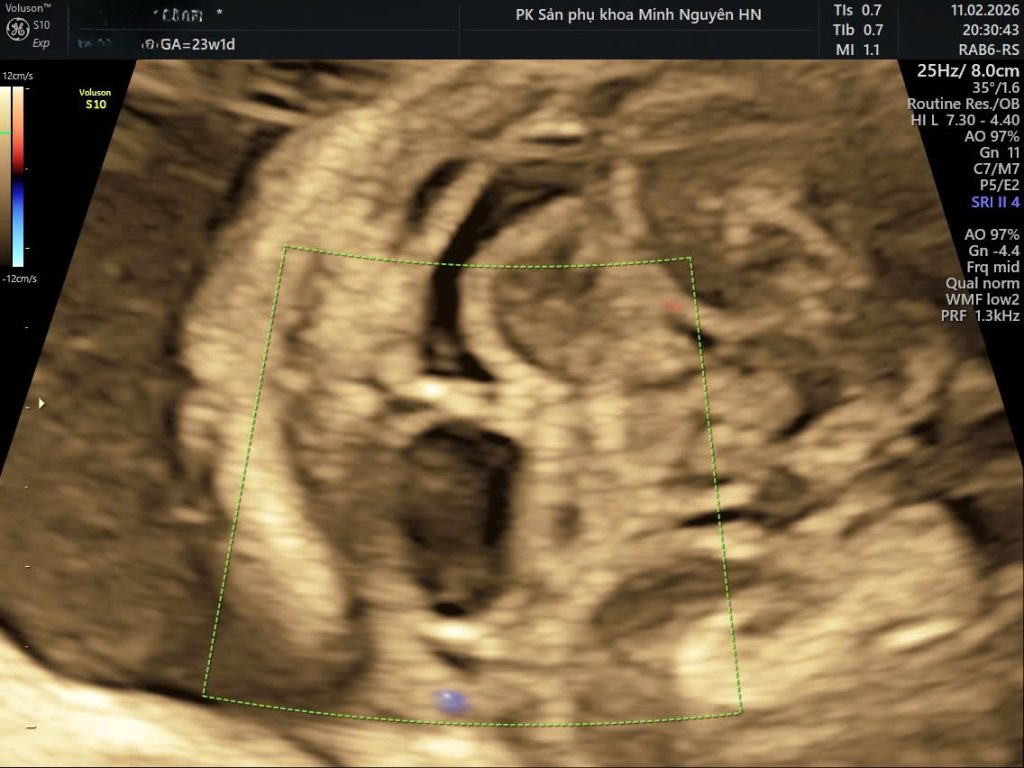

Mặt cắt quan trọng nhất khi đánh giá nang hố sau

Mặt cắt dọc giữa (midsagittal view) là mặt cắt vàng.

Trên mặt cắt này, bác sĩ có thể thấy rõ:

- Hình thái thùy nhộng

- Não thất IV

- Bể lớn hố sau

- Lều tiểu não

Nếu chỉ dựa vào mặt cắt ngang, rất dễ chẩn đoán nhầm.